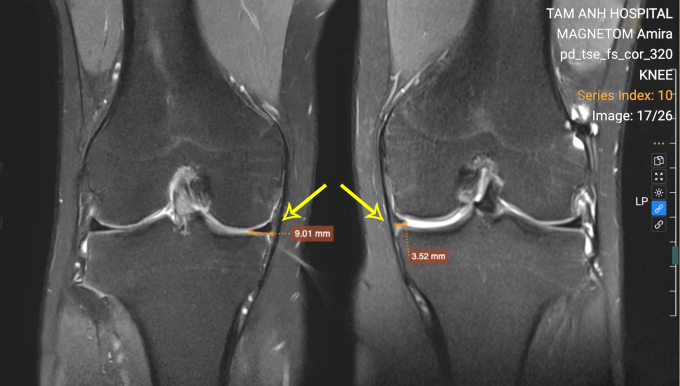

ThS.BS Nguyễn Quang Tôn Quyền, Phó khoa Chấn thương Chỉnh hình, ghi nhận phim chụp cộng hưởng từ MRI cho thấy dây chằng chéo trước của Quang được tái tạo chắc chắn nhưng sụn chêm trong đã bị cắt bỏ toàn bộ dẫn đến cảm giác lỏng gối.

Khớp gối trái của Quang khuyết thiếu sụn chêm trong so với gối phải. Ảnh: Bệnh viện Đa khoa Tâm Anh